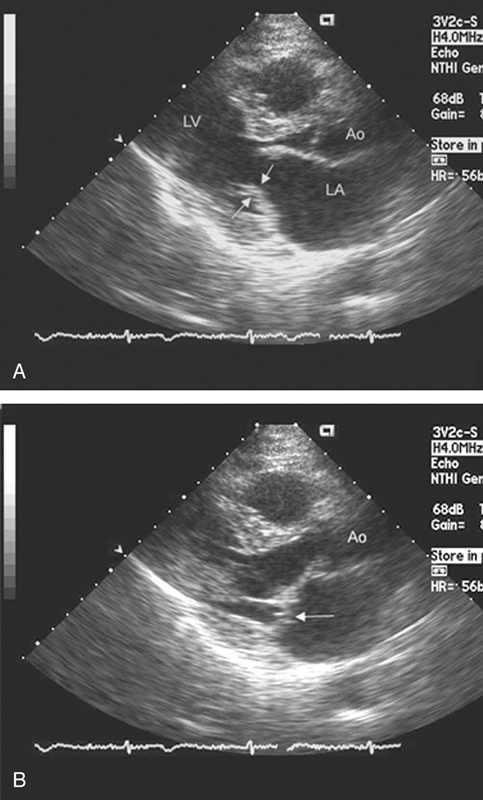

فحوصات تشخيصية لبعض امراض القلب والشرايين التاجية